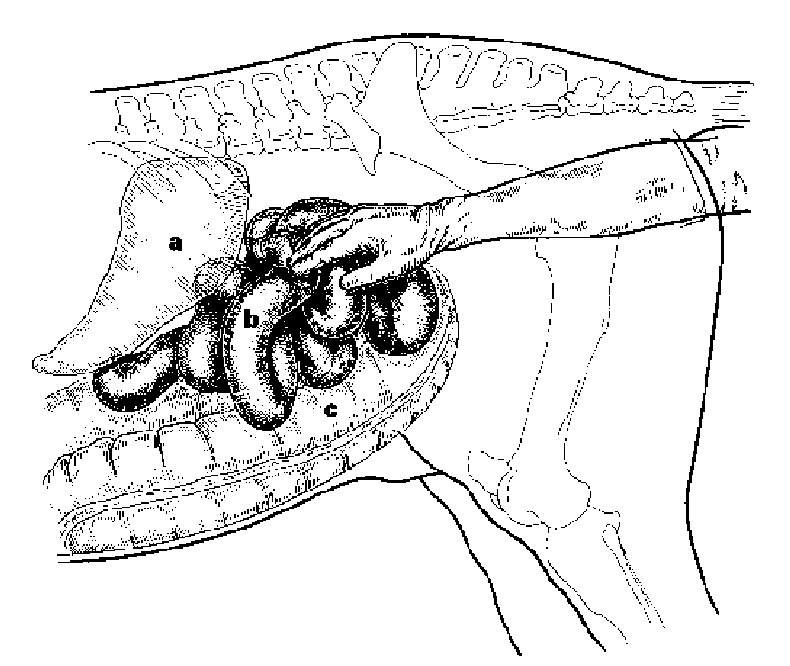

small intestine distension

blown up w/ fluid & gas, always feels abnormal (normally its smooth, texture is abnormal)

enterolith

stones of calcium and magnesium in intestine, common in southwest, usually in right dorsal colon theyre single